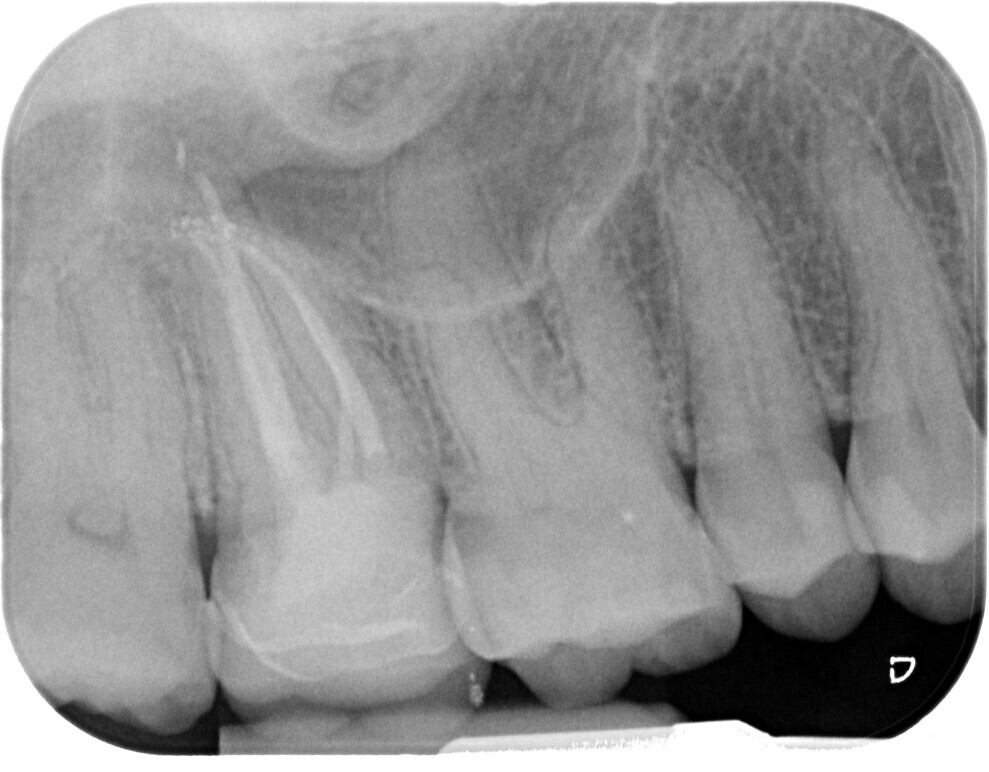

Fig. 4: Canal system shaped and cleaned before obturation.

The current approach is towards a conservative access cavity that can guarantee enough visibility inside the pulp chamber to carry out shaping, irrigation and obturation, the pillars of endodontics. The first step to preparing an access cavity with these characteristics is the clinical and radiographic assessment of the tooth to be treated. The clinician should carefully evaluate the following important aspects that can yield valuable information for the approach to access cavity preparation: the position and inclination of the tooth (Figs. 6 & 7), the 3D extension of the carious process if present, the quality of pre-existing restorations and the relationship to the periodontium.